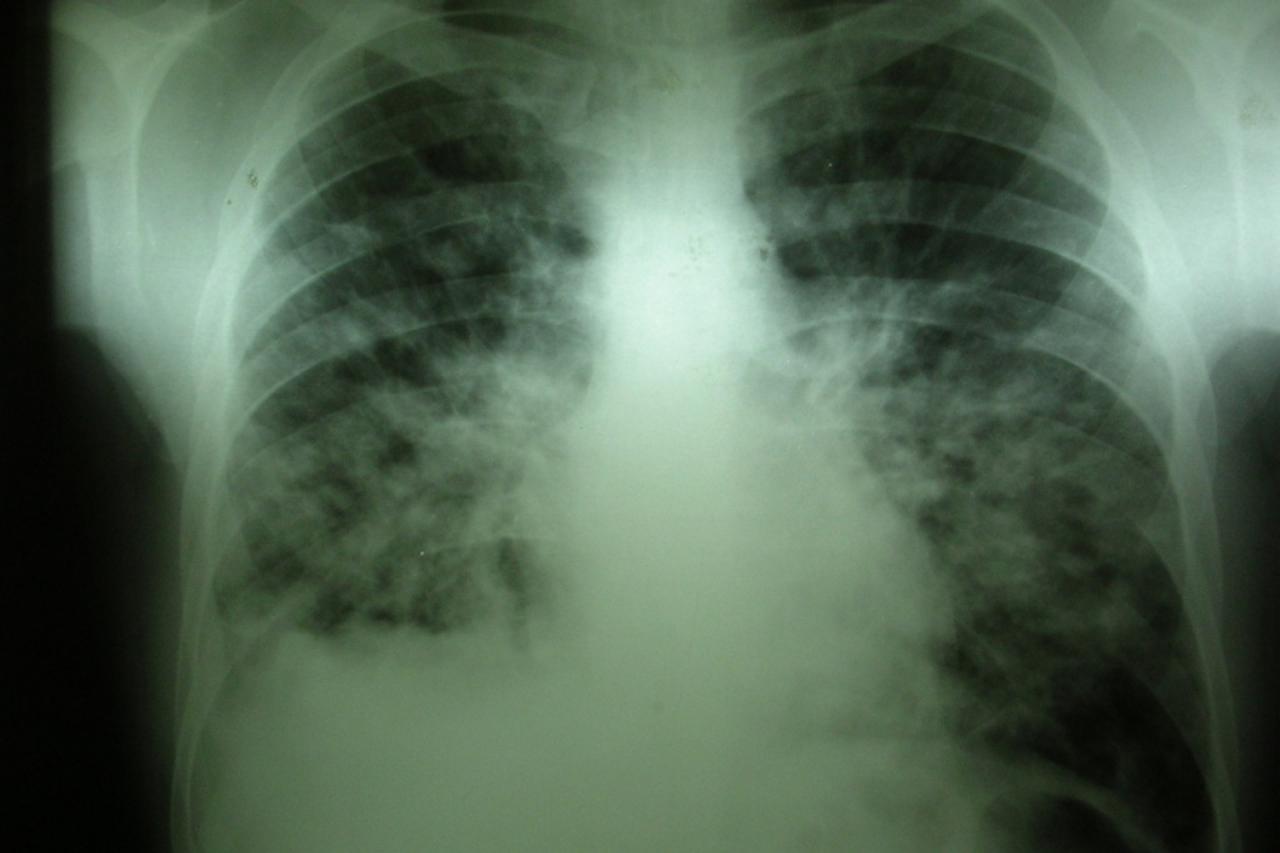

(Ne)ukroćen bacil TBC nije prošlost. U Karlovcu se lani liječilo 45 pacijenata Karlovačka županija među vodećima je u Hrvatskoj po broju oboljelih od te zarazne bolesti